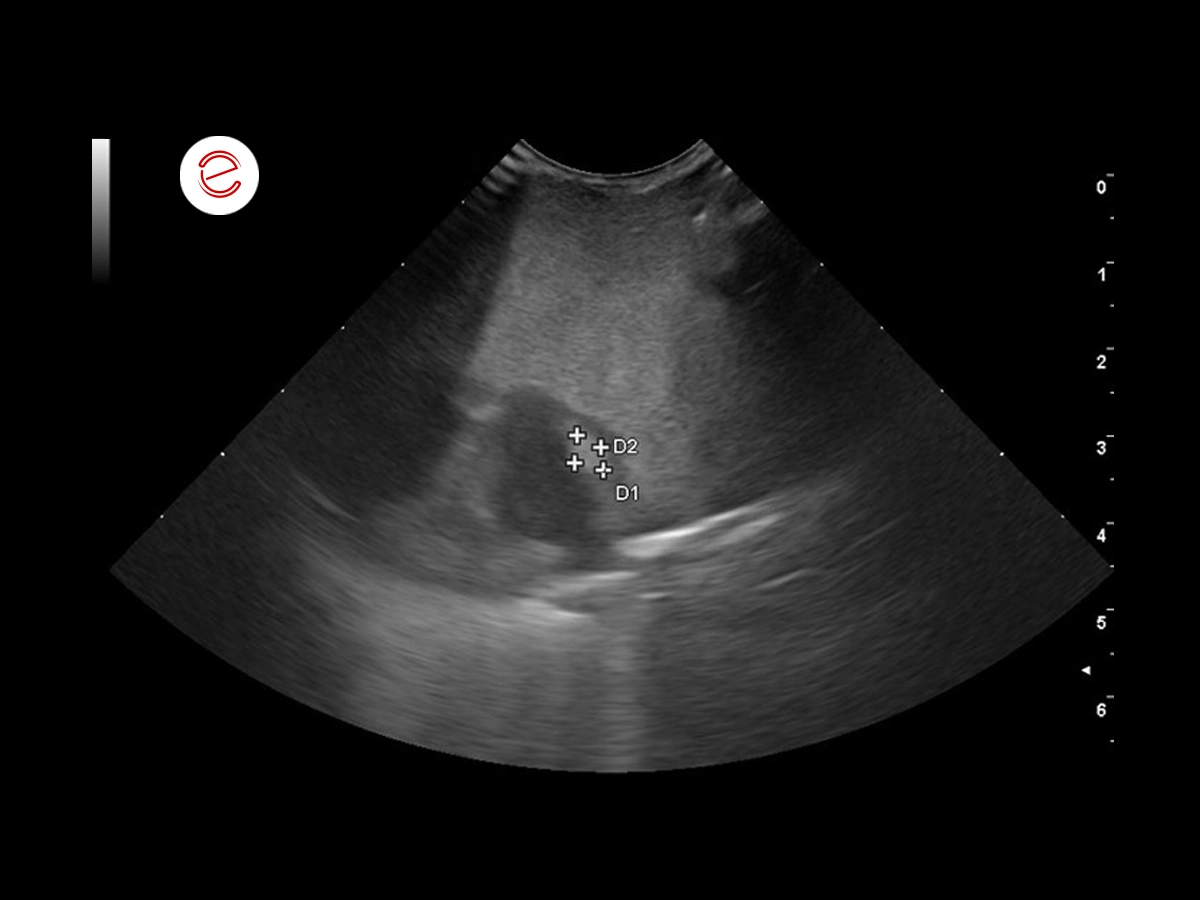

Measurement of the mass within the myocardium of the left ventricle.

Differential diagnoses include a granuloma (fungal or bacterial), neoplasia and hematoma.